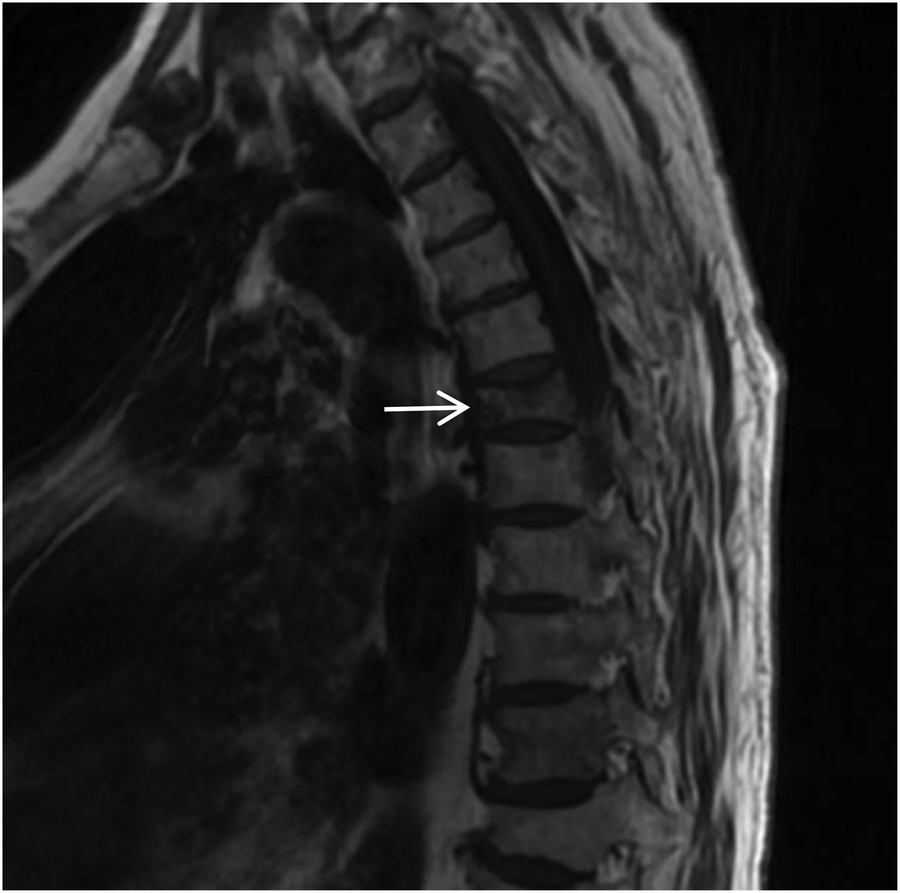

A spinal orthopedic consultation was requested to analyze the persistent back pain. The orthopedic surgeon recommended magnetic resonance imaging (MRI) of the thoracic spine. The MRI results revealed a T6 vertebral compressive fracture accompanied by bone marrow edema and adjacent soft tissue edema (Figures 15, 16). Based on these findings, the acute chest pain was attributed to a fresh compressive fracture of the T6 vertebra. CTA and chest CT incidentally identified absence of RPA, accompanied by characteristic pulmonary vascular and parenchymal manifestations, supporting the diagnosis of congenital isolated right pulmonary artery agenesis. This diagnosis was further supported by the absence of intracardiac abnormalities on echocardiography.

Figure 15

Sagittal T1-weighted MRI of the thoracic spine shows a flattened T6 (white arrow) vertebral body with patchy low signal within the vertebral body.

Figure 16

Sagittal STIR MRI of the thoracic spine shows high signal within the T6 (white arrow) vertebral body, with patchy high signal shadows in the soft tissues of the back at the same level.

Following admission, comprehensive investigations were completed. The electrocardiogram was essentially normal. Laboratory findings were as follows: High-sensitivity C-reactive protein (hs-CRP) 4.97 mg/L (elevated); Serum amyloid A (SAA) 11.75 mg/L (elevated); Neuron-specific enolase (NSE) 16 ng/ml (elevated); Interleukin-6 (IL-6) 10.03 pg/ml (elevated). Coagulation profile, D-dimer, renal and liver function tests, fasting blood glucose, myocardial enzyme profile, and procalcitonin (PCT) were within normal limits. N-terminal pro-B-type natriuretic peptide (NT-proBNP) was 230 pg/ml. The clinical diagnosis revealed the following: 1. Acute T6 vertebral compression fracture. 2. Congenital isolated right pulmonary artery agenesis. 3. Bronchiectasis with infection. 4. Stable COPD. Following a comprehensive evaluation, the T6 fracture was identified as the cause of the acute chest pain, and congenital right pulmonary artery agenesis was identified as the cause of the respiratory pathology. The patient received concurrent antibiotic treatment for a respiratory infection and was moved to the spinal surgery department for percutaneous vertebroplasty (PVP). Postoperatively, the patient's pain resolved, and respiratory conditions stabilized. She was discharged after six days.

Thoracoabdominal aortic CTA and chest CT findings are illustrated in Figures 1–14. There was no evidence of aortic dissection. The right pulmonary artery was absent distal to approximately 3 cm from the bifurcation, with a smooth and rounded defect margin. The main pulmonary artery and its major branches showed no abnormal densities. No right pulmonary artery branches were observed in the right lung. Multiple tortuous arterial branches from the right subclavian artery, descending aorta, and right renal artery supplied the right lung. The right hemithorax was smaller, with localized pleural thickening and adhesions bilaterally. Multiple bronchiectasis with thickened walls and patchy, nodular, and linear opacities encircled the right lung. Increased translucency and several hyperlucent regions were visible in the left lung. CT imaging findings demonstrated: 1. Congenital absence of the right pulmonary artery (RPA), with the right lung supplied by collateral circulation originating from the right subclavian artery, right intercostal arteries, and the right renal artery. 2. Right pulmonary hypoplasia, bronchiectasis of the right lung, accompanied by infection and partial consolidation in the right upper lobe, compensatory hyperinflation of the left lung, and multiple bullae in the left lung. 3. Bilateral localized pleural thickening and adhesions. 4. Osteoporosis and mild flattening of the T6 vertebra and compression fractures of T11 and T12.